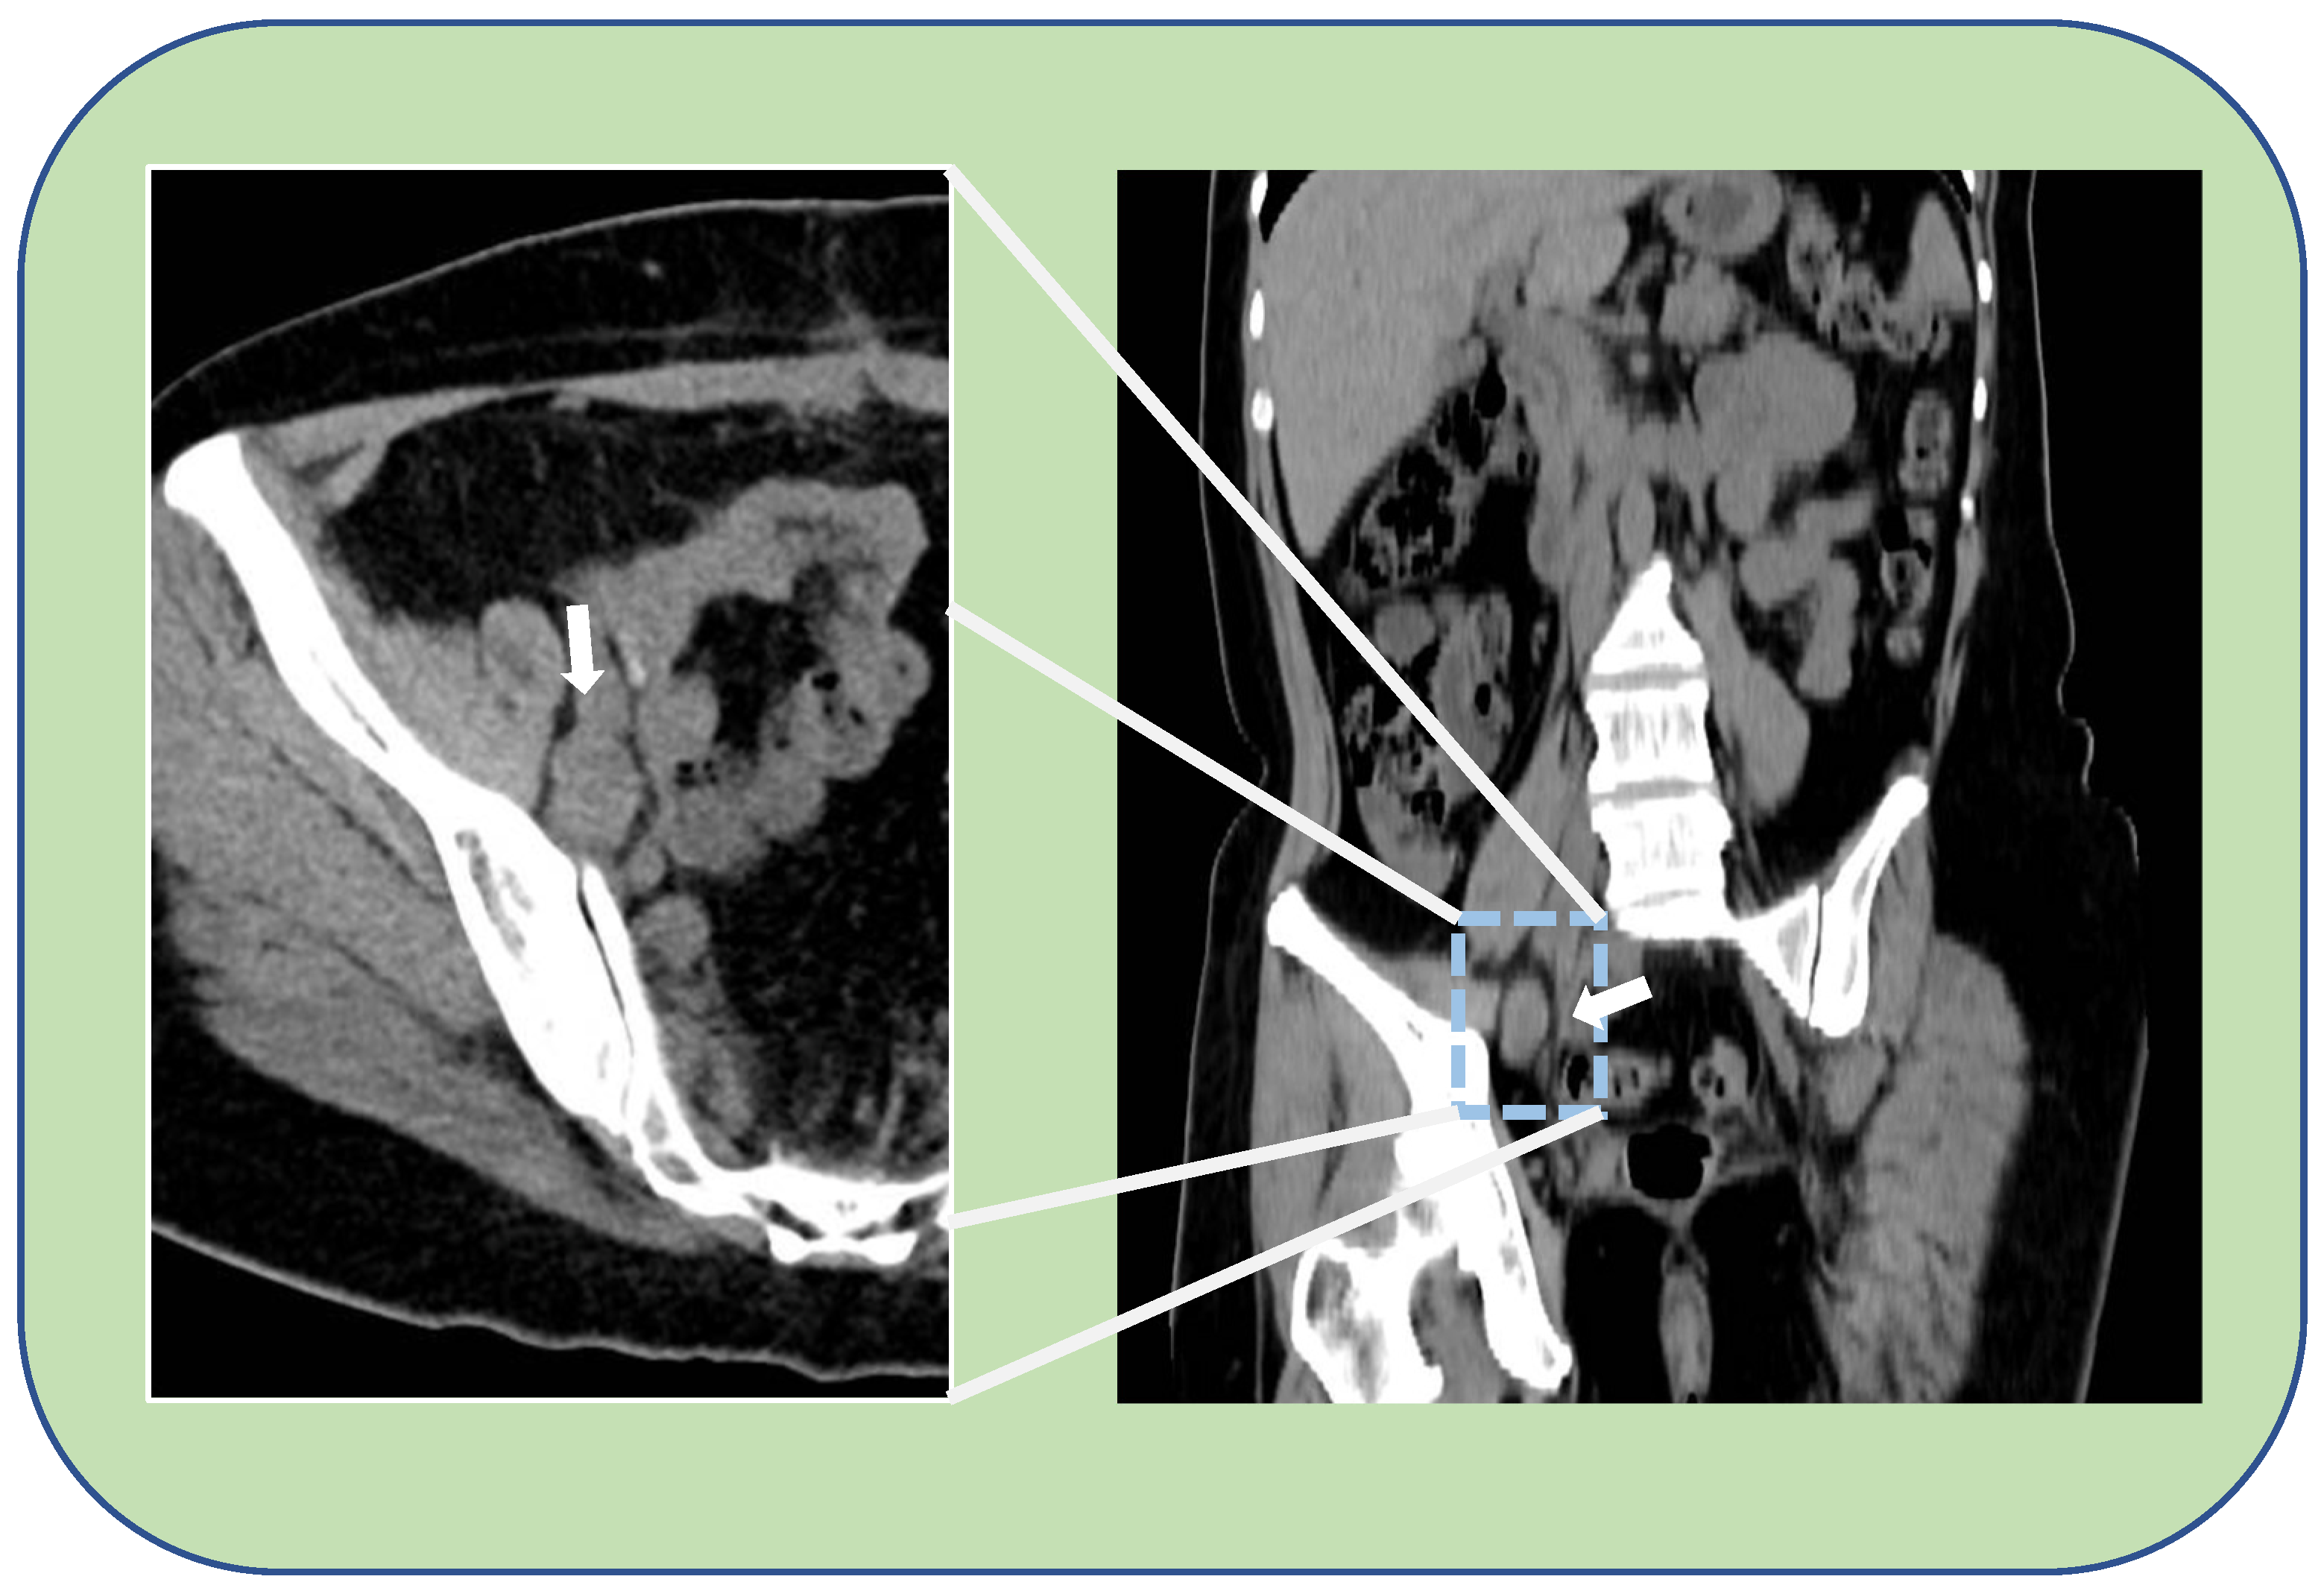

After 12 months of platinum-free interval an isolated pelvic peritoneal recurrence occurred. Additional six cycles of platinum-based chemotherapy were administered achieving complete disease remission. She was successively diagnosed with a germ-line BRCA 2 mutation. A further recurrence occurred 15 months after the end of second-line chemotherapy. For this, she underwent to surgical management with pararectal node excision, hepatic node excision and diaphragm nodes ablation by laparotomy, with an optimal residual tumor (CC-1). Three cycles of platinum-based chemotherapy followed the surgery, and Olaparib was administrated until it was discontinued, 24 months later, following an episode of transient subocclusion, managed with nonsurgical treatment. After further 22 months, a PET-CT scan revealed FDG uptake (SUV 6.9) at a right external iliac increased node (24 mm in maximum diameter) in correspondence with the obturator nerve (Figure 1). The trans-obturator recurrence was also confirmed by a transvaginal ultrasound (TV-US) performed by an ultrasonographer with a high expertise in the field of oncological gynecology (Figure 2). She was thus scheduled for surgery at our Center in consideration of the absence of blood vessels invasion, the single site of recurrence and previous therapy with PARPi.

Figure 1.

Thick white arrow shows an enlarged, pathologic, lymphnode of about 2 cm in the right obturator region. On the left, a detail of the right half-pelvic cavity on the axial view. On the right, a coronal view of the CT-PET performed during the follow-up.